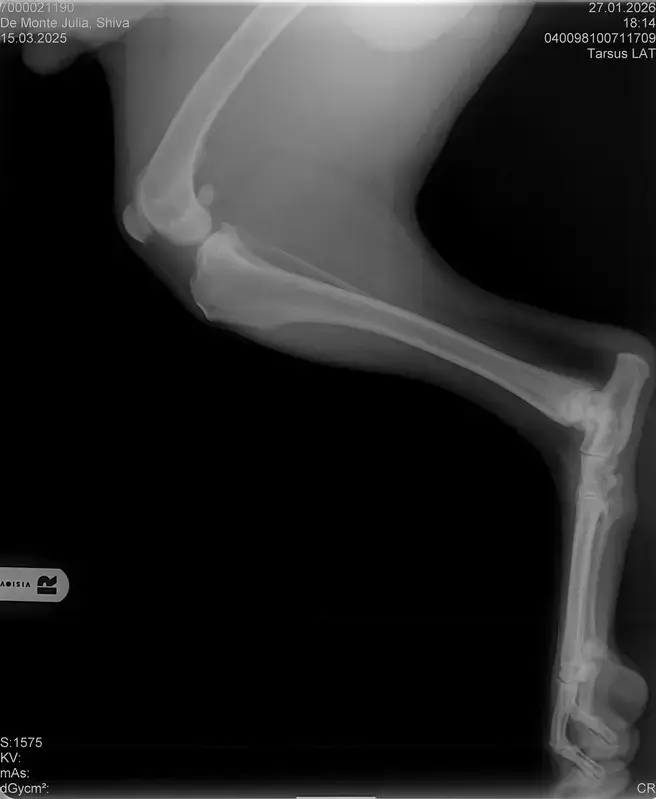

Vorige Woche kam mir Shiva verändert vor, nicht der aufgeweckte Spaßvogel der er sonst ist. Ich dacht vl ist er im Garten iwie blöd ausgerutscht weil unser gesamtes Grundstück über Wochen von einer dicken Eisschicht überzogen war. Er lag viel rum, zuviel da er doch zu den Wirbelwinden unter den Junghunden gehört. Er quetschte sich zum schlafen an mich ran, was auch untypisch für ihn ist. Er ist immer so „iiiii fass mich nicht an“. Ich nehms ihn nicht böse er ist nicht der große Kuschler :D Hat er wohl von mir :D :D aber er pickte nur an mir dran, ruhen ohne Körperkontakt war nicht möglich. Fand ich schön aber da ich wusste dass es nicht Shiva ist machte ich mir schon Sorgen… Am nächsten Tag wollte ich ihn bürsten alles war wie immer, er legte sich hin und sah mir zu wie ich einen Fellberg stapelte. Bei seinen Hinterpfoten hörte ich auf und dachte mir ich fühl mal vorsichtig.. Plötzlich knurrte er mich an vor Schreck weil ich damit überhaupt nicht gerechnet hatte zuckte ich reflexartig zurück (was lt Trainerin ein Fehler war)… Aber ich hab nicht mit einer derartigen Reaktion gerechnet, Shiva hatte schon 2 kleine Verletzungen die ich ohne Probleme verarzten konnte. Am nächsten Tag gings ab zum TA. Mit Maulkorb da ich nichts riskieren wollte. Nach der Untersuchung wo er auch mehrmals knurrte gings ab zum röntgen. Und das riss mir den Boden unter den Füßen weg. Dann die Aussage von der TA „ich weiß sie wollen einen gesunden jungen Hund aber das ist Shiva leider nicht“. Was jetzt? Er ist so ein aufgewecktes Kerlchen, absolute Lieblingsbeschäftigung ist Parcour. Er macht es so gern, ja auch UO und Suchspiele aber das leuchten in seinen Augen wenn wir Geräte machen :( (er macht noch keine schweren Geräte wie A Tafeln oder springen… Aber die seichten macht er mit absoluter Leidenschaft.. Ruhe halten über mehrere Monate… nur langsames gehen oder schnüffeln.. puh ich weiß nicht wie ich ihm verbieten soll zu rennen und zu toben… Vl habt ihr Tipps für mich. Im Anhang der Befund und ein paar Bilder vom kleinen Wirbelwind. <3

• Naja die Diagnose kommt von einem „Facharzt“, lt TA war ihrerseits alles i.O. Sie wollte noch sicher gehen und die Bilder zur weiteren Befundung einschicken und das kam dabei raus. Und der Therapievorschlag beläuft sich auf Ruhe, Ruhe und noch mehr Ruhe. Und einer Schmertherapie von Gabapentin 800mg 1/2 Tablette 2x tgl, Carprodyl 120mg 1 1/2 Tabletten 1x tgl und TamaCan CBD Tropfen 10-15 Tropfen 2x tgl. 1x in der Woche soll ich telefonisch Auskunft geben wie es Shiva geht. Das ganze mal für 14 Tage. Sie meinte noch sie hat viele Junghunde die ein Leben lang Schmerzmittel nehmem müssten. Die Röhrenknochenentzündung heilt in der Regel von selber der Rest gehört beobachtet… Ich weiß im Moment auch nocht so recht.. Er tut mir nur wahnsinnig leid mit sovielen Diagnosen und für mich war erstmal vorrangig ihn schmerzfrei zu bekommen. Das ist er inzwischen und versteht die Welt nicht mehr warum er nicht wie sonst spielen und arbeiten darf. Im Anhang noch Röntgenbilder falls sich jemand damit auskennt bzw Interesse hat..

• Ok, die Röntgenbilder sind aber auch extrem schlecht.

Panostitis ist idR sehr schmerzhaft, aber nicht unüblich und heilt in der Regel von alleine aus, wichtig dabei ist schonen und Entzündungshemmer zu geben, damit das nicht chronisch wird. Ich denke, dass die Akut bemerkbaren Schmerzen hauptsächlich davon kommen. Also da passt die Empfehlung deiner TÄ für's Erste auf jeden Fall.

Wenn dieser Panostitis-schub rum ist, würde ich dem Rest nochmal nachgehen. Man kann bei Dr. Tellhelm ( SV Gutachter) ein privatgutachten in Auftrag geben, das kostet um die 100€. Da kriegst du halt ne konkrete Einstufung und nicht "verdacht auf" und "könnte hiermit ODER damit in Verbindung stehen", etc.

Ich denke aber, dass du für ein Gutachten von Tellhelm nochmal neu röntgen lassen musst, ich finde, dass das Bild der Hüfte (HD und LÜW wird da beurteilt) und die Draufsicht auf die Ellenbogen (nötig zur Beurteilung von ED) unterirdisch sind!